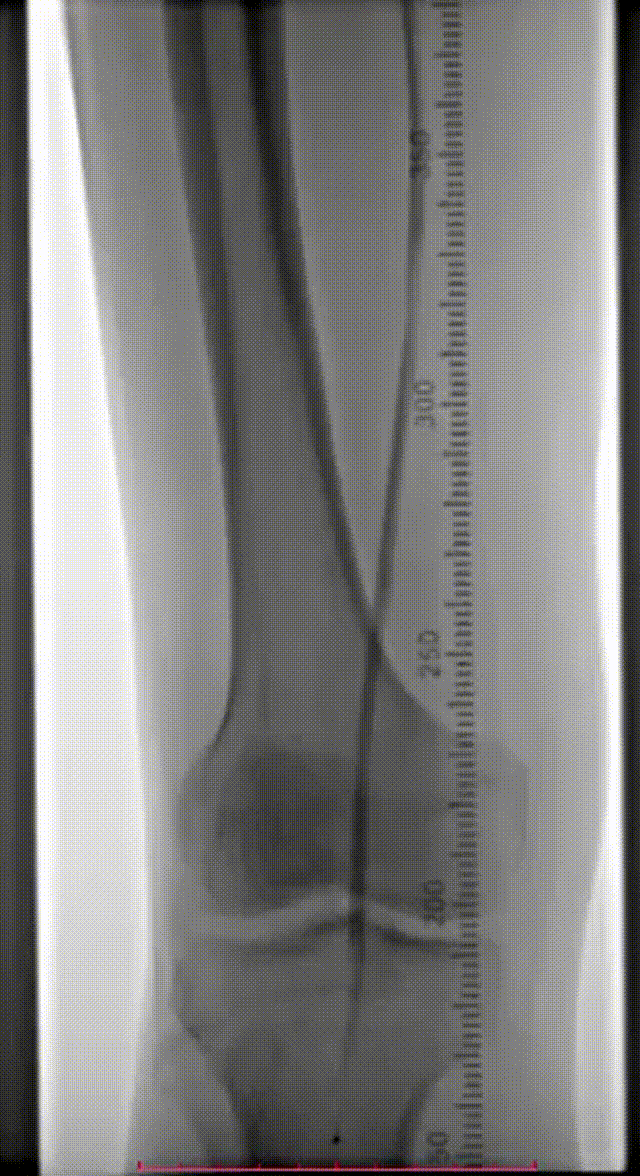

患者为70岁男性,因“右下肢活动后疼痛2月余”入院。

查体:股动脉(左++,右++),腘动脉(左+,右-),胫后动脉(左+,右+),足背动脉(左-,右-)。

既往史:糖尿病、高血压、高脂血症、慢性乙型病毒性肝炎、左肝癌术后右肝复发癌。

辅助检查:ABI(左0.72,右0.56),下肢动脉彩超显示双下肢动脉硬化伴多发斑块,右侧股浅动脉上段闭塞,双侧胫前动脉中下段接近闭塞。CTA提示:腹主动脉粥样硬化,右侧股动脉、双侧胫前动脉中重度狭窄、闭塞,左侧股动脉、双侧腓动脉、胫后动脉轻度狭窄,左侧髂内动脉局限性闭塞。

术前CTA

术前造影